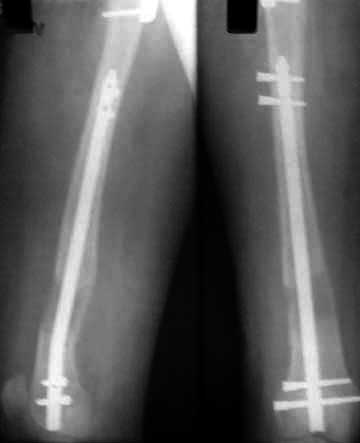

Following this an Ilizarov frame was applied on the lower femur over the nail. The construct had one and a half ring above the corticotomy and one ring below the corticotomy. (Pictures 05 and 06).

One week after the corticotomy the distraction was started. After about a week there was no visible distraction taking place at the corticotomy and hence under anaesthesia distraction was checked using imaging. After making sure that distraction is taking place patient was returned to the ward and distraction continued(picture 07).

Patient was discharged from hospital and distraction continued at home. After lengthening upto a difference of 0.5cm shortening (4.5cm lengthening) (pictures 08 and 09),

the fixator was removed along with locking of the proximal part of the nail (picture 10).

Total duration of fixator was about two months. In view of the osteotomy of the upper femur, weight bearing was delayed for six weeks and then encouraged to tolerable limits.

The knee movements though encouraged were not progressing till the fixator was removed (pictures 11 and 12).

However after the fixator came off, the range of movement increased significantly. The last review at about eight weeks after the fixator removal showed good regenerate at the distraction site and good progress of the knee movement (pictures 13, 14 and 15).